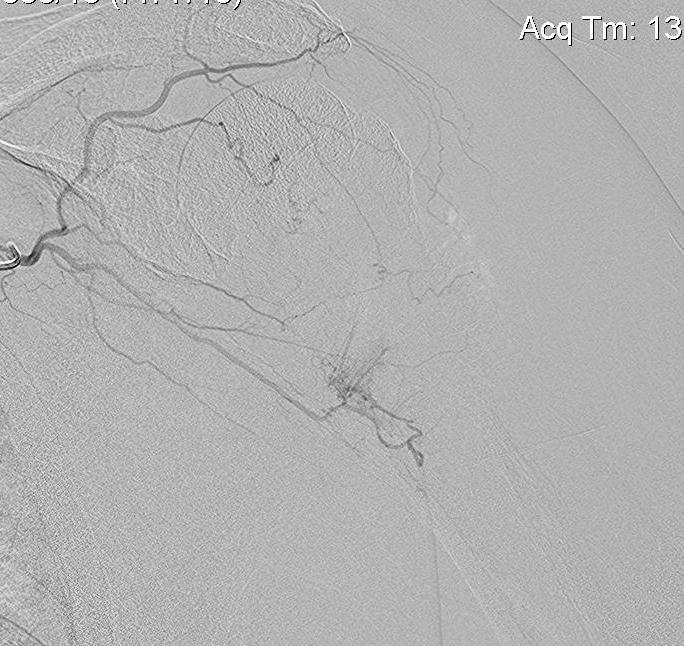

Pre-operative Arterial Embolization

Indications

- renal cell carcinoma

- thyroid carcinoma

Results

- embolisation of RCC metastasis in 107 patients

- success in 96%

- all patients had variable ischemic pain for 2 - 4 day

- 41 cases with embolization prior to surgery compared to 41 cases without

- embolization reduced blood loss, transfusion, and surgical times